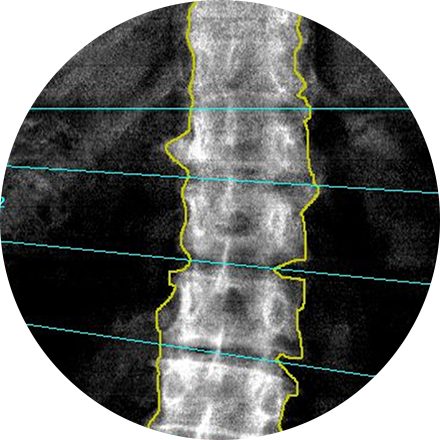

Bone Density Scan (DEXA)

A dual-energy X-ray absorptiometry (DEXA) scan measures the density and mineral content in bone, most often in the hip or lower spine. It is the most accurate method of determining bone density and potential problems related to bone loss. This test is a valuable tool for diagnosing osteoporosis, which often has no symptoms until you suffer a fracture. A bone density scan can diagnose the disease at its earliest stages, which means you can begin receiving treatment to protect your bones sooner.